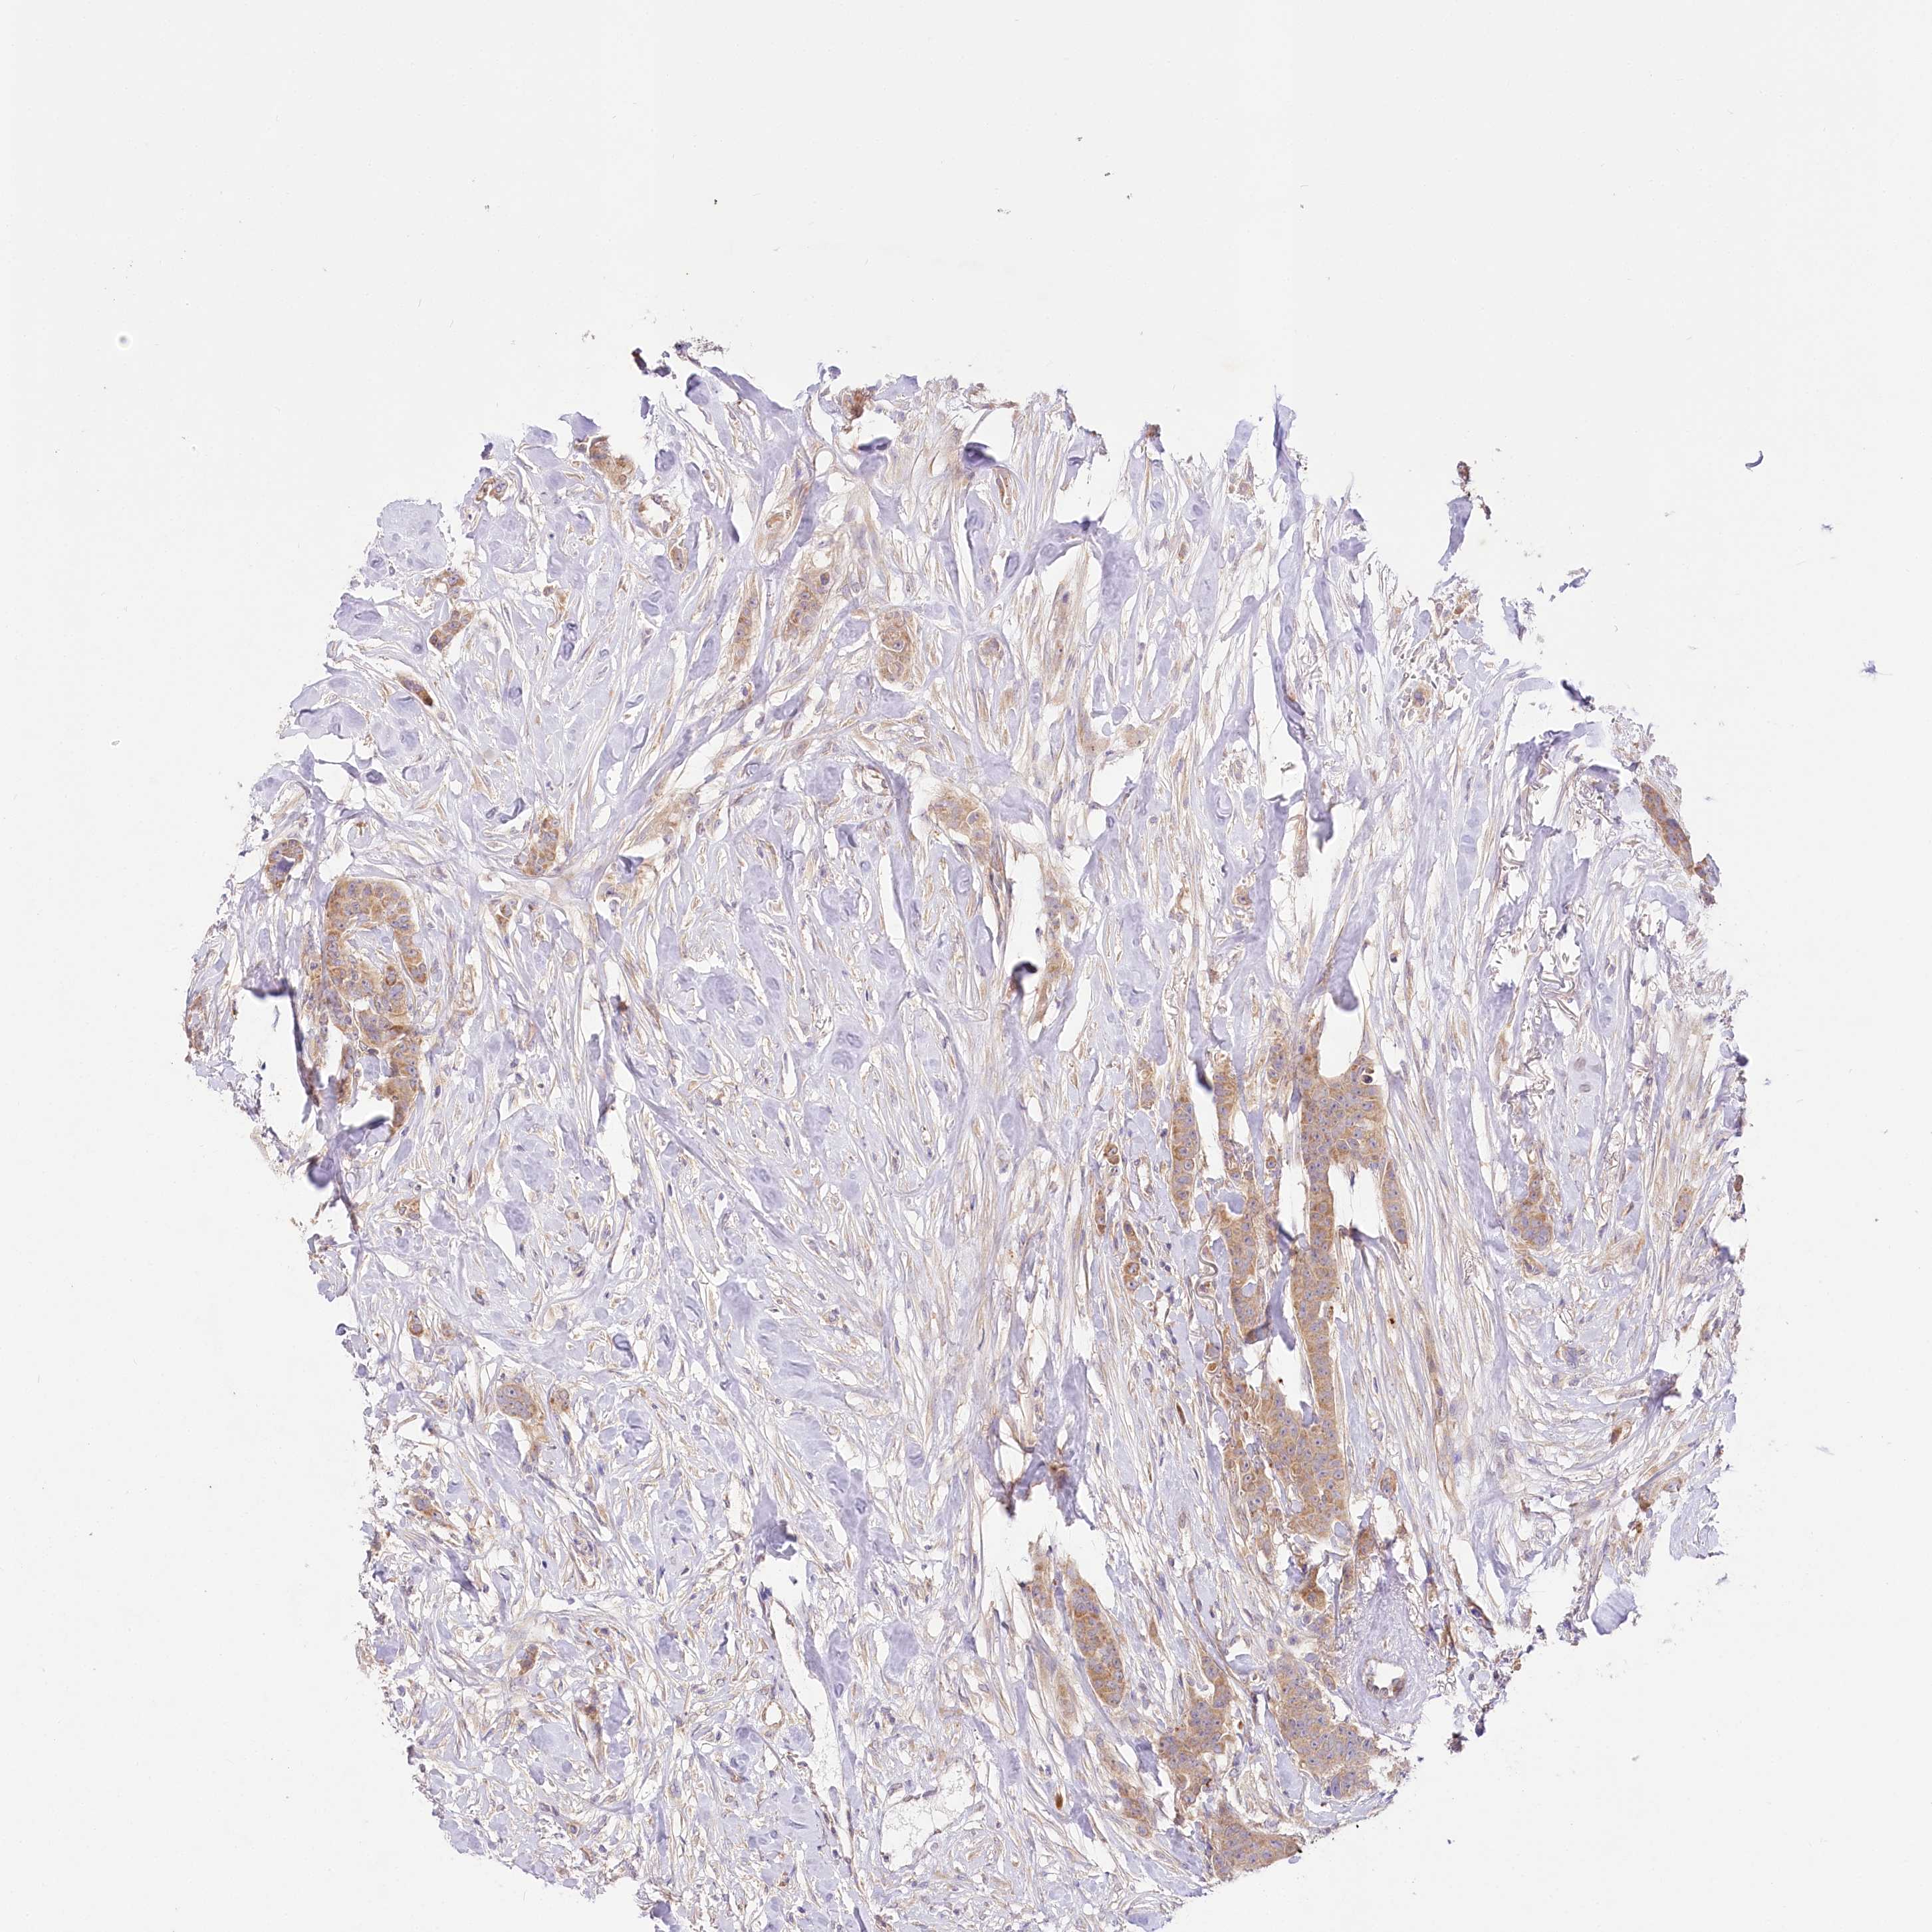

BRCA TCGA BRCA VALIDATION PROTEIN EXPRESSION

ANTIBODIES

AND

VALIDATION